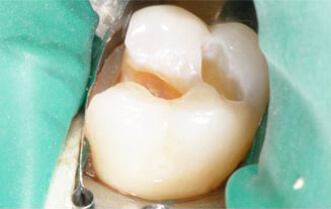

Probleem. Hambakaariese tekitatud kahjustused

Lahendus. Kaariese kahjustuste taastamine komposiittäidetega.